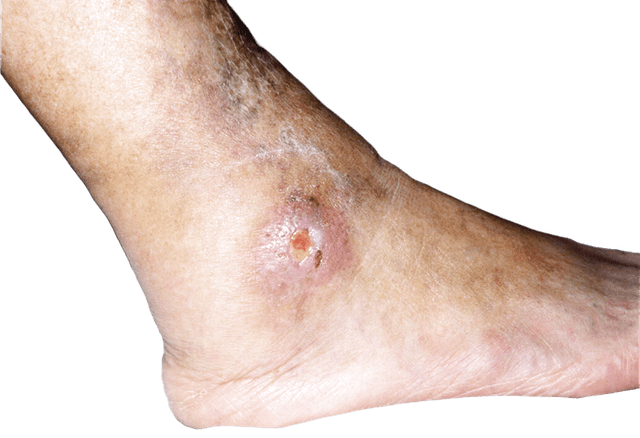

Venösa bensår: Beror på att blodet har svårt att transporteras tillbaka till hjärtat, vilket leder till svullnad, inflammation i huden som förtunnas och till slut sårbildning. Såren sitter oftast på insidan av underbenet nära ankeln och är ytliga, fuktiga och omgivna av missfärgad hud.

Arteriella bensår: Orsakas av dålig blodtillförsel till benen, ofta på grund av åderförkalkning. De uppstår vanligtvis på fötter, tår eller hälar och är djupa, smärtsamma och torra med nekrotisk (död) vävnad.

Bensår kan variera i utseende beroende på orsaken. Venösa sår är ofta ytliga, fuktiga och omgivna av missfärgad hud, medan arteriella sår är djupa, torra och smärtsamma. Diabetiska sår sitter ofta på fötterna och kan ha sämre känsel runt sig.